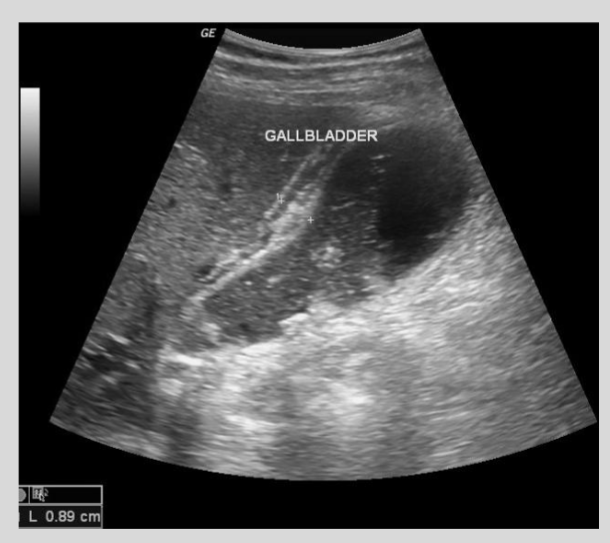

Describe the preferred radiologic approach to detect gallstones and acute cholecystitis

Ultrasound is the first choice modality to detect gallstones and diagnose acute cholecystitis, showing echogenic stones and gallbladder wall thickening

What does a positive 'sonographic Murphy sign' indicate?

A positive sonographic Murphy sign is maximal tenderness elicited by the ultrasound probe directly over the gallbladder, indicating acute cholecystitis.